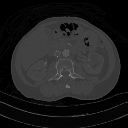

Maximum Intensity Projection

We've described the maximum intensity projection (MIP) earlier in the context of axial projection, where the maximum voxel value is determined for lines running in parallel through the projected slice thickness. A sequence of such images can be generated when this computation is applied at successive angles around the voxel data. One simple sequence is a rotating one for 360 degrees around the horizontal plane, as illustrated in the left panel of the figure below, where the maximum intensity is projected for every 9 degrees around the patient and the resultant 40 images compiled into a repeating, temporal (e.g. movie) sequence:

Notice that the 3D MIP derives its information from the most attenuating regions of the CT scan (given that the CT-number is directly dependent on the linear attenuation coefficient) and hence portrays bone, contrast media and metal with little information from surrounding, lower attenuating tissues. Notice also that continued viewing of the rotating MIP sequence can generate a disturbing effect where the direction of rotation appears to periodically reverse – which may be an aspect of perceptual oscillation. The perspective MIP, illustrated in the panel on the right in the above figure, can reduce this limitation by providing spatial cues which can be used to guide continued visual inspection.